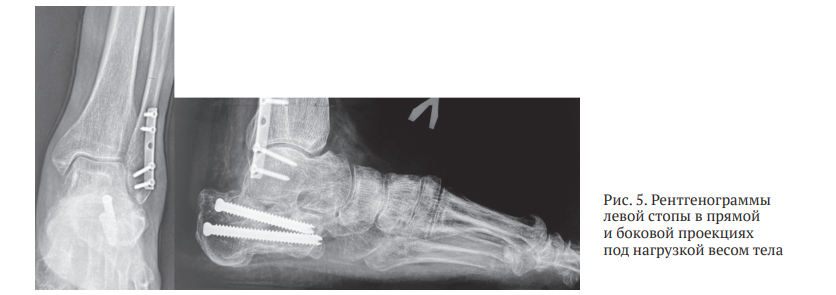

Пациенту проведено рентгенологическое исследование, по результатам которого выявлены: посттравматический остеоартроз подтаранного сустава левой стопы (3 стадия по Kellgren – Lawrence); отрицательный угол Белера, указывающий на нарушение анатомии пяточной кости; «горизонтализация» таранной кости и снижение таранно-пяточной высоты, обусловленные посттравматическими изменениями; консолидированный перелом левой пяточной кости 4 типа по Zwipp – Rammelt с фиксацией винтами и сращением фрагментов в положении смещения; консолидированный перелом малоберцовой кости, фиксированный металлоконструкцией (пластина и винты) после травмы 2002 г. Феномен «горизонтализации» таранной кости стал причиной прогрессирующего ограничения тыльного сгибания в левом голеностопном суставе, что привело к формированию переднего импиджмента в данной области (рис. 5).

Для уточнения хода линий перелома, взаиморасположения и степени консолидации фрагментов пяточной кости пациенту выполнена МСКТ левой пяточной кости, в ходе которой подтвержден исходный суставно-депрессионный характер перелома, выраженный пяточно-малоберцовый конфликт, а также уточнены форма и взаиморасположение консолидированных фрагментов пяточной кости и металлоконструкций (рис. 6).